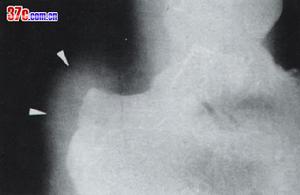

(2)排除骨折或類風濕侵蝕性跟骨變化,由於表現具有相似之處,幫對在鑑別上常藉助一些輔助檢查,最常用的是X線檢查,可直接發現病損的地方。